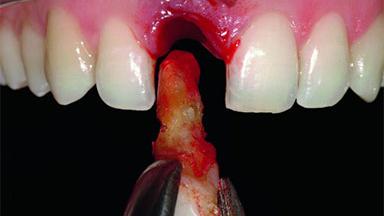

A 32-year-old female Caucasian patient with a compromised maxillary right central incisor was referred to us by a general dentist. Her chief complaints were discomfort and mobility of tooth 11 with unsatisfactory esthetics due to discoloration. The patient reported a previous trauma, some years earlier, as the origin of pathology on the afflicted tooth. Anamnesis was negative for any other dental or periodontal pathology in the remaining dentition. The patient did not take any medication and reported to be a light smoker (5–10 cigs/day). She had high esthetic expectations of her treatment. The extraoral examination revealed a high smile line with full exposure of her maxillary teeth and surrounding soft tissue in the area between the second premolars.

Bone Augmentation Horizontal|Simultaneous|Staged

Augmentation Materials Autogenous chips|Xenogenous|Membrane

Bone Volume Deficient horizontally, requiring prior grafting